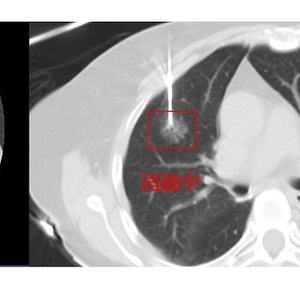

图说:上海市胸科医院“一针”射频消融,为多原发性肺癌患者解疑难 来源/采访对象提供

经过细致准备与精准定位,陈阿姨的射频治疗开始了。术中,在CT引导下,医生手中的“消融针”按照既定路线“穿行”,快速、准确地到达病灶部位,进行了精准地消融,新发的肿瘤细胞一下子就被超高温成功灭活了!由于几乎没有创伤,陈阿姨恢复得很好,术后第二天就出院了。